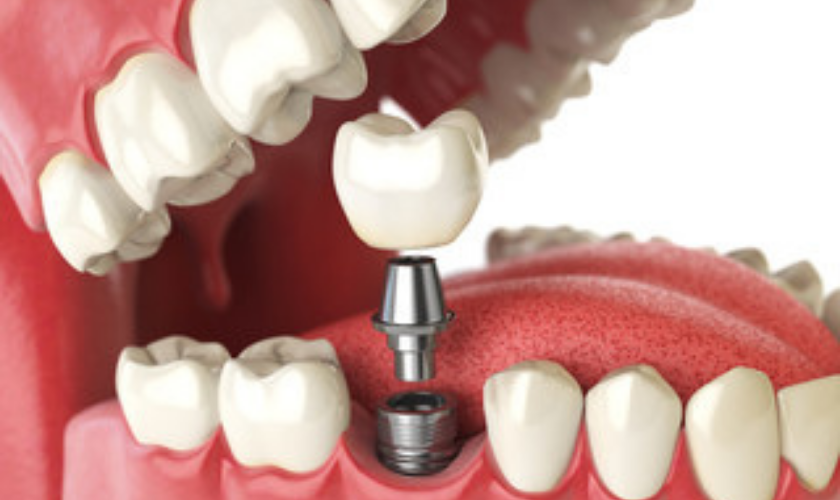

Dental Implants

SAME DAY DENTAL IMPLANTS